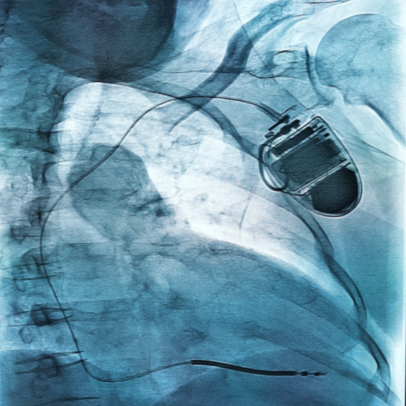

目前尚没有试验证实任何药物或其他方法能完全有效的预防Brugada综合征引起的猝死,惟一被证实为肯定有效的方法是植入ICD(植入型心律转复除颤器)。

ICD是目前惟一证实能够预防Brugada综合征猝死的有效方法,药物和射频导管消融等治疗只能作为辅助治疗方法,以减少ICD放电次数,提高病人的生活质量,不宜单独使用。